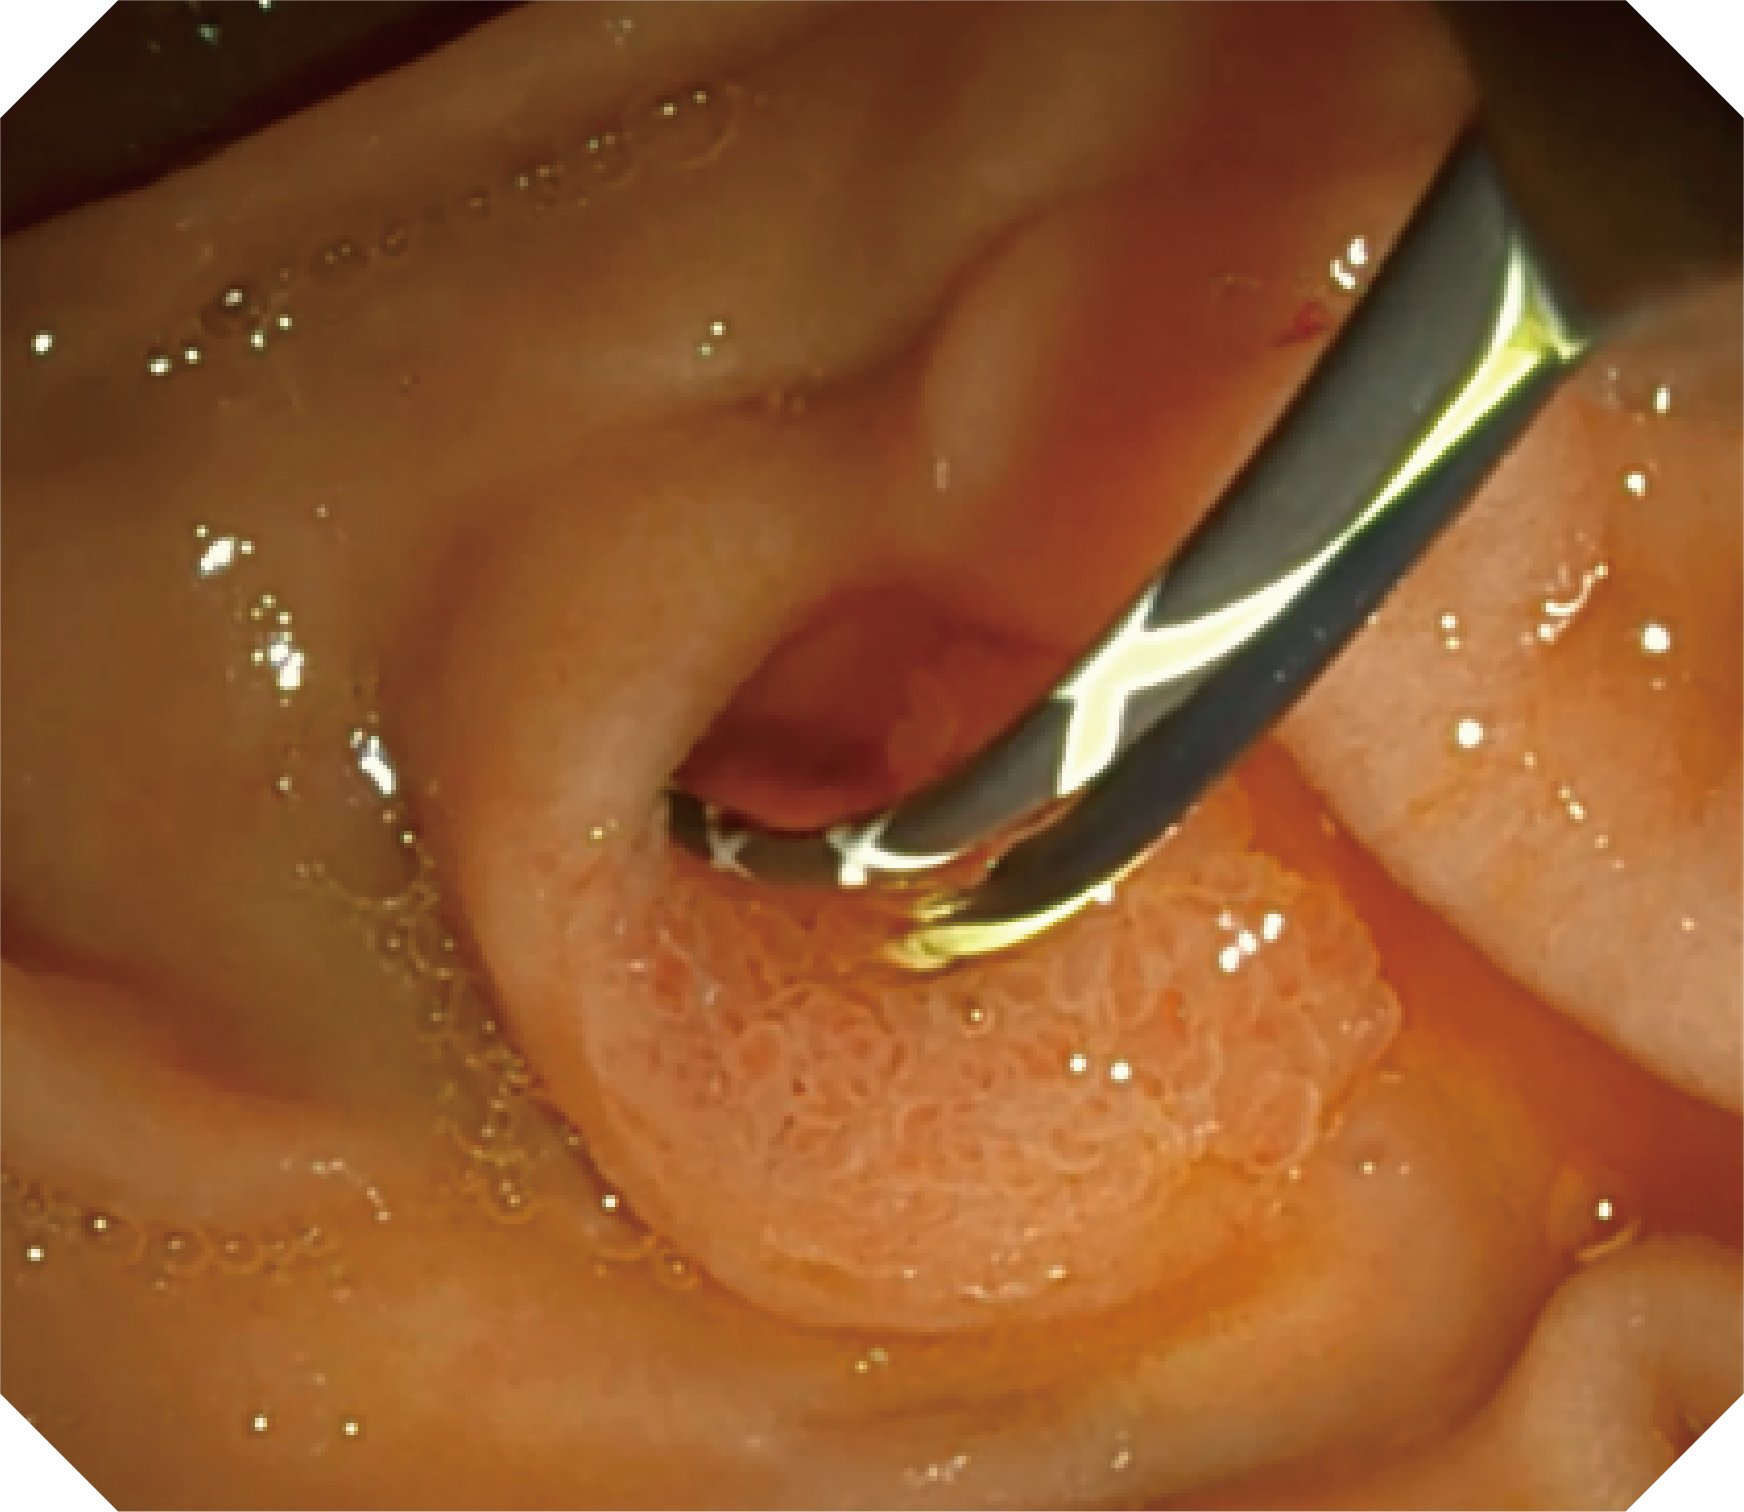

优异的手术器械抬举性

更好的通过性,更稳定的镜体支撑力

当切开刀伸出视野外时,导向面引导其回归视野